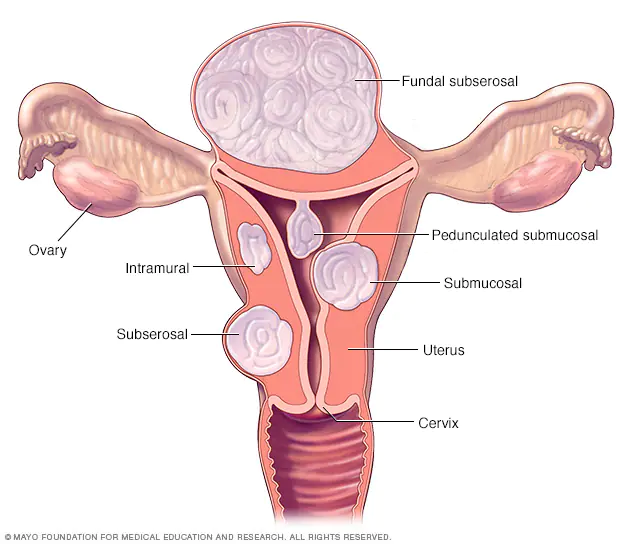

Diferentes tipos de fibromas uterinos y su ubicación

-Ubicación de los fibromas

Los fibromas uterinos suelen clasificarse por su ubicación. Los fibromas intramurales crecen en la pared muscular del útero. Los fibromas submucosos crecen en la cavidad uterina. Los fibromas subserosos se forman en el exterior del útero.